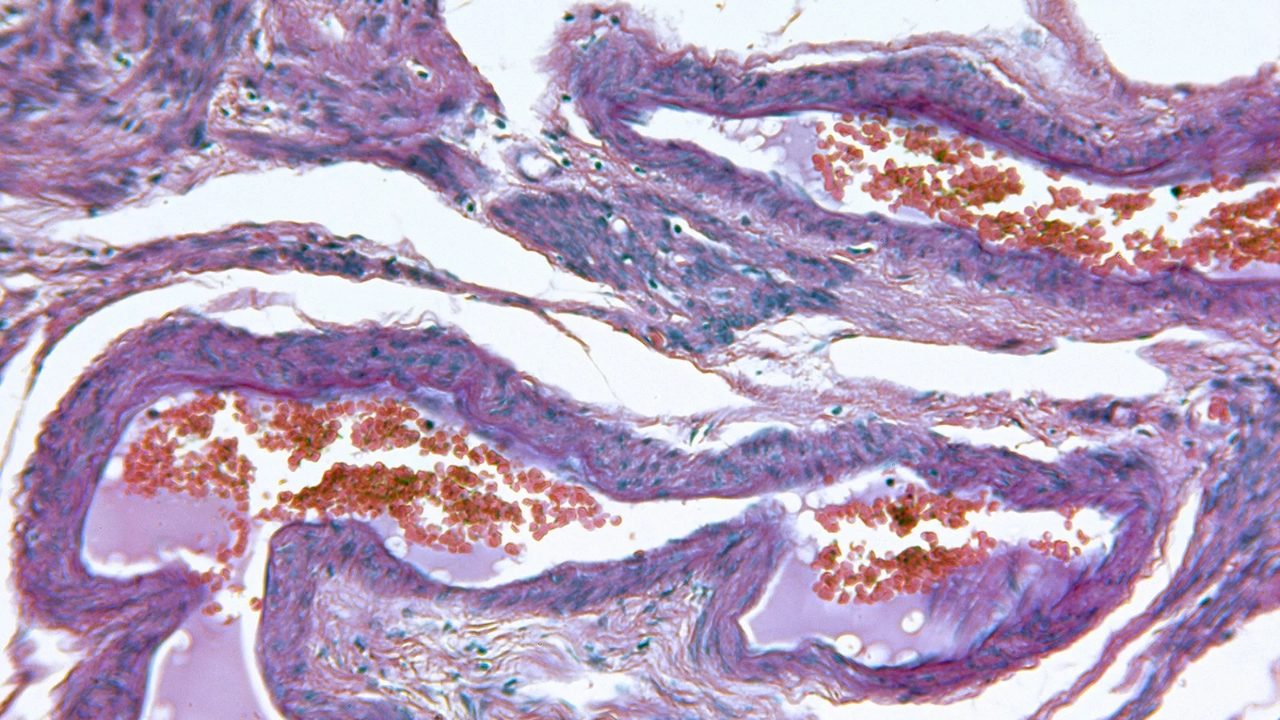

El VPH se puede detectar por medio de un estudio que puede hacerte tu ginecólogo o médico funcional, conocido como Papanicolau. Este estudio además de detectar la presencia del Virus del Papiloma Humano (VPH), también permite detectar si existe algún cambio o anormalidad en las células del cérvix que pudieran indicar la existencia de células pre cancerígenas.